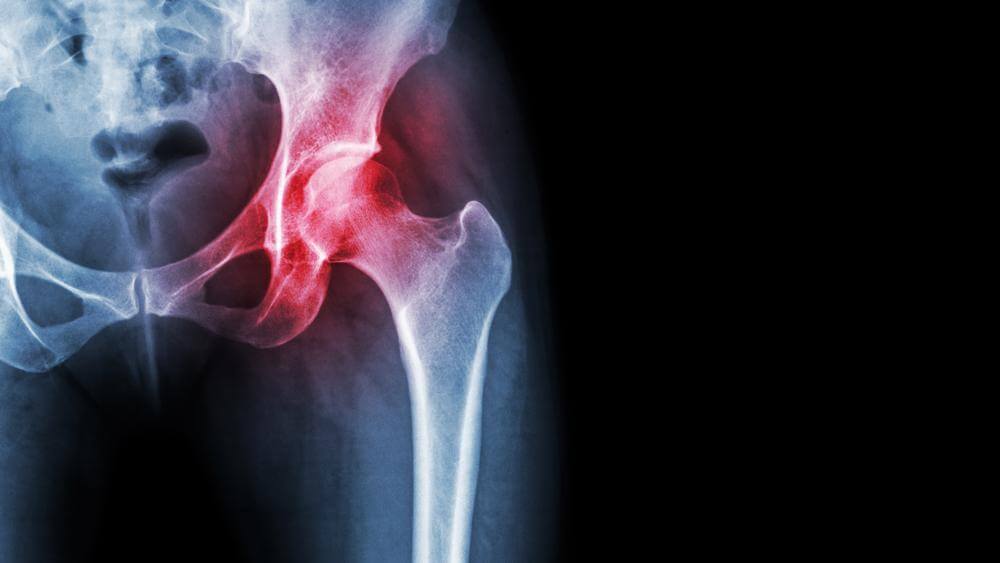

تعویض مفصل لگن به همراه تمامی نکات آن